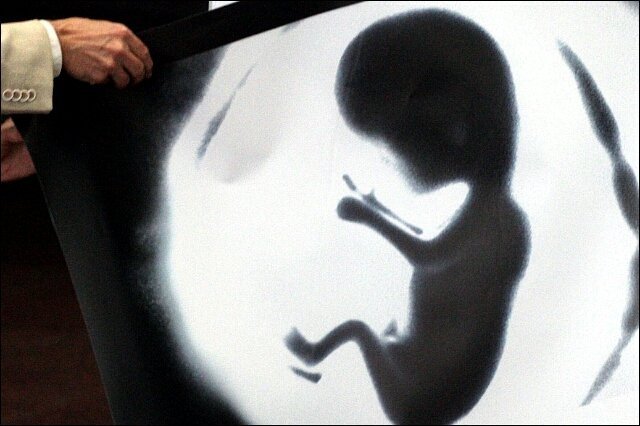

Якими малюнками на пачках цигарок лякатимуть курців. ФОТО

Всі упаковки тютюнових виробів в Україні від 4 жовтня повинні виготовлятися з фотоілюстраціями із зображеннями хвороб, які викликає куріння.

50% передньої частини пачки буде займати напис: "Куріння вбиває", а із зворотного боку на 50% розміститься графічне зображення з попереджувальним написом.

Всього буде використовуватися 10 варіантів графічних попереджень з відповідними коментарями.